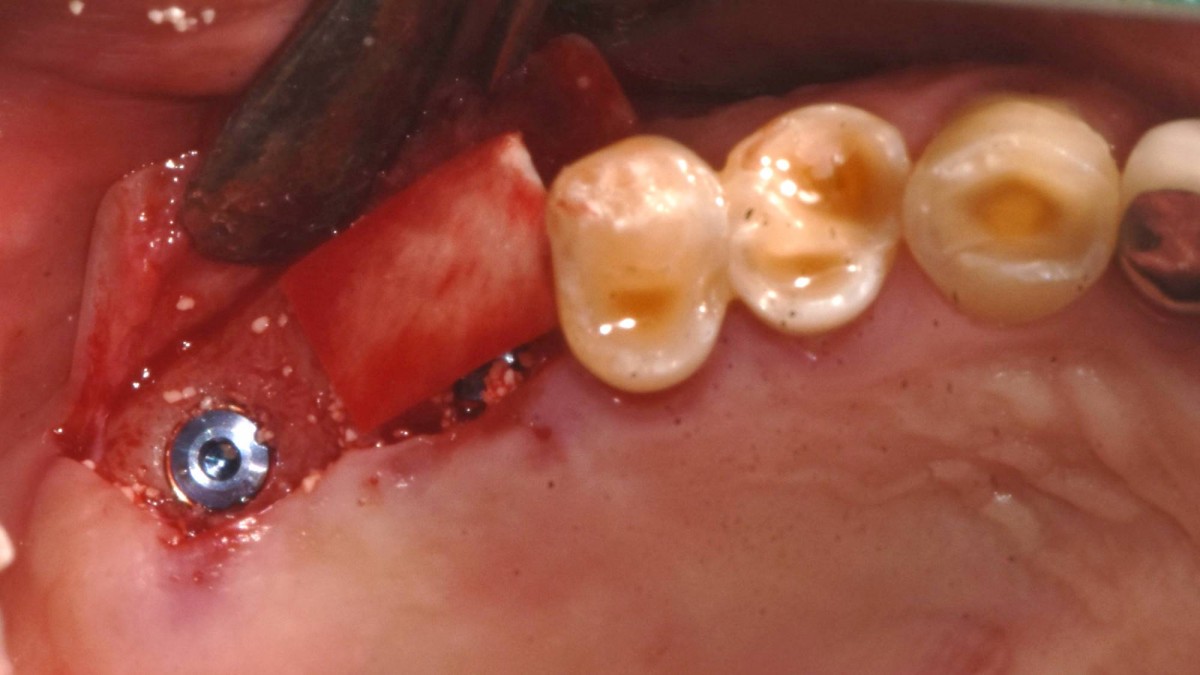

Socket Lift and Implant Placement in the right maxilla.

<GCacg> A 56-year-old male patient complained of pain in the right upper and lower jaws. And he wanted the upper first molar to be pulled out first.